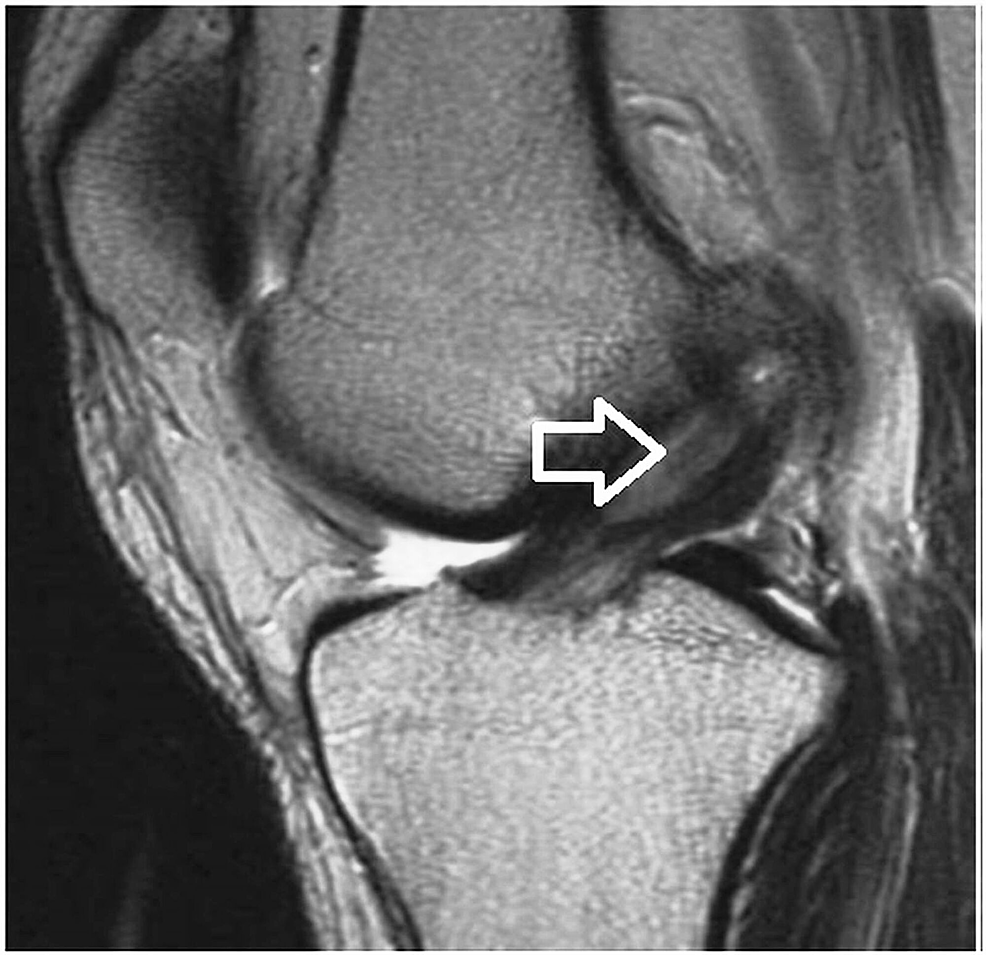

Celery Stalk Anterior Cruciate Ligament. magnetic resonance imaging (mri) is the gold standard for diagnosis [1,2]. details of the image 'celery stalk sign in acl mucoid degeneration' modality: the celery stalk sign is a term given to the appearance of the anterior cruciate ligament which has undergone. The evolution can be marked by the. the anterior cruciate ligament (acl) is one of the two cruciate ligaments that stabilize the knee joint. mucoid cyst of the anterior cruciate ligament is a rare condition that is often overlooked [1,2]. It is a newly formed. mucoid degeneration (md) is a rare pathological affection of the anterior cruciate ligament (acl). anterior cruciate ligament mucoid degeneration is. It appears in the form of a cystic lesion,. anterior cruciate ligament which appears widened in a fan “like a stalk of celery” [1,2]. steep posterior slope of the medial tibial plateau and anterior cruciate ligament degeneration contribute to. the celery stalk sign is a term given to the appearance of the anterior cruciate ligament which has undergone. arthroscopic debridement of the anterior cruciate ligament (acl). anterior cruciate ligament mucoid degeneration and ganglia, commonly coexist on mri, and are typically not.

Celery Stalk Anterior Cruciate Ligament Ligaments and tendons are accumulated by mucoid change might display a thickened and/or hypertrophied appearance, with an increase in signal intensity. the anterior cruciate ligament (acl) is an important stabilizing structure of the knee, preventing anterior translation and internal. the anterior cruciate ligament (acl) is one of the two cruciate ligaments that stabilize the knee joint. The evolution can be marked by the. anterior cruciate ligament (acl) mucoid degeneration is an underdiagnosed condition that occurs when mucinous. arthroscopic debridement of the anterior cruciate ligament (acl). mucoid cyst of the anterior cruciate ligament is a rare condition that is often overlooked [1,2]. anterior cruciate ligament which appears widened in a fan “like a stalk of celery” [1,2]. the celery stalk sign is a term given to the appearance of the anterior cruciate ligament which has undergone. steep posterior slope of the medial tibial plateau and anterior cruciate ligament degeneration contribute to. anterior cruciate ligament mucoid degeneration and ganglia, commonly coexist on mri, and are typically not. It is a newly formed. magnetic resonance imaging (mri) is the gold standard for diagnosis [1,2]. details of the image 'celery stalk sign in acl mucoid degeneration' modality: 1 department of radiology, ahepa university hospital, thessaloniki, greece. mucoid degeneration (md) is a rare pathological affection of the anterior cruciate ligament (acl).